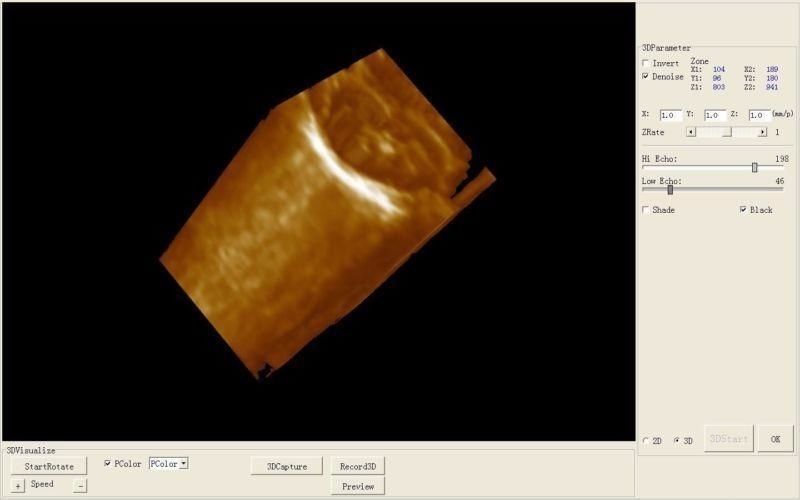

3D Ultrasound Capabilities

The integration of 3D imaging technology in the Laptop Ultrasound scanner transforms the diagnostic experience. This feature not only enhances image clarity but also provides a comprehensive view of anatomical structures, making diagnosis more reliable. Doctors can identify issues earlier and more accurately because they can see three-dimensional representations of organs. This capability is particularly important in prenatal care and gynecological assessments, ensuring better health outcomes for patients.